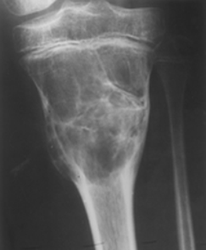

Fig 141. Quiste óseo aneurismático.

Rx AP. Lesión expansiva en la metáfisis tibial, con aspecto en pompas de jabón, por quiste ose aneurismático.